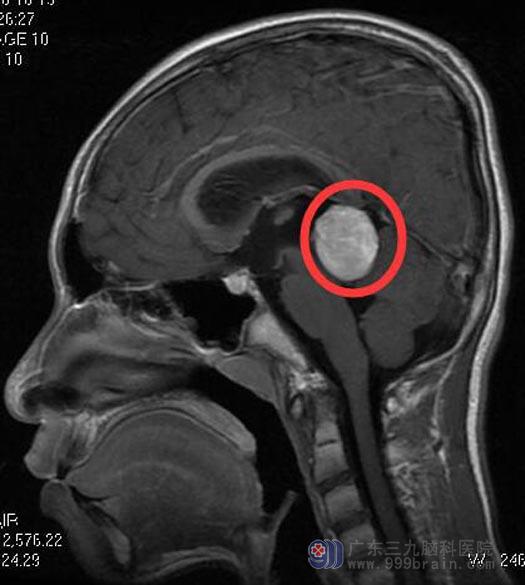

入院时小凯精神萎靡,颈稍强直,闭目难立症(+)。头颅MR检查结果:松果体区占位性病变,大小约2.6cm×2.2cm×2.7cm,邻近第三脑室后部及脑干受压变形,中脑导水管受压变窄,幕上脑室扩张。结合他的病史,鲁明主任考虑卵黄囊生殖细胞瘤可能性大,家属要求手术治疗。

▲手术前